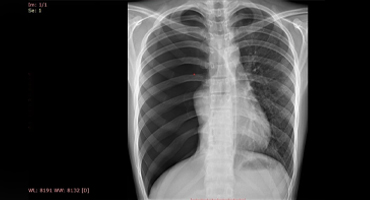

Rayos X

NEUMOTORAX ESPONTANEO